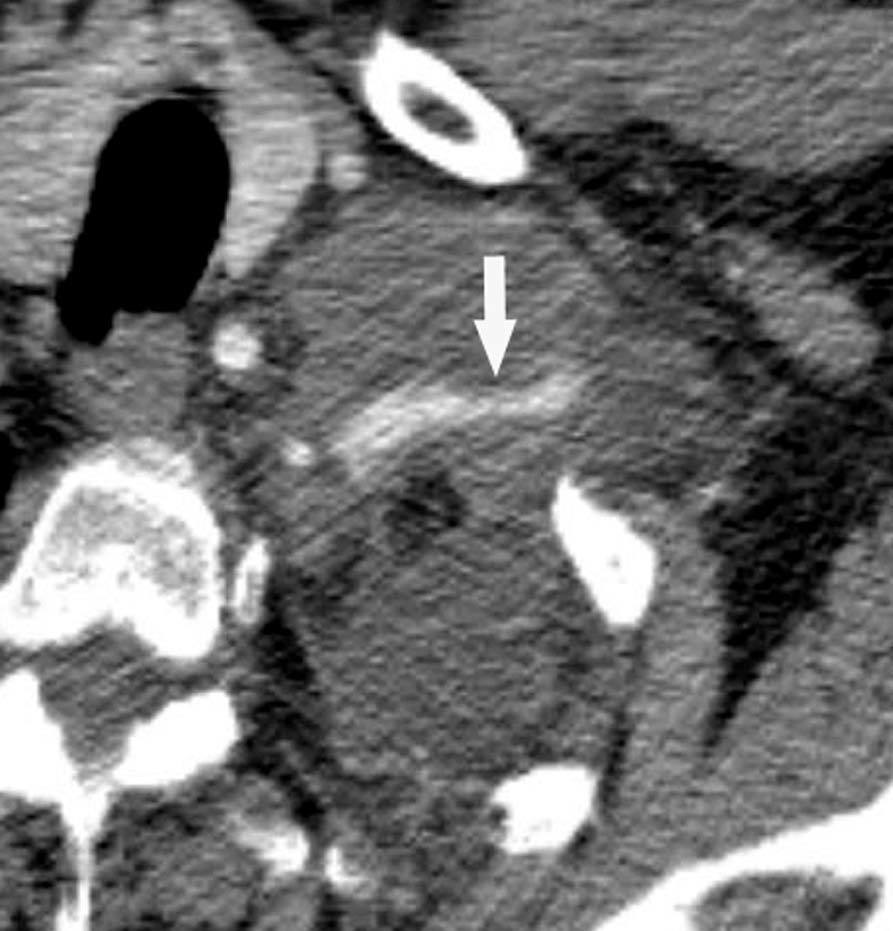

Pese a las conocidas limitaciones de la TC, ésta continúa siendo la técnica de elección en la estadificación del tumor en los pacientes con CPNM; su sensibilidad y especificidad en la determinación de la infiltración de pared oscilan entre el 38 y el 87% y del 40 al 90%, respectivamente, según las series. El desarrollo de nuevos equipos de TC helicoidal y principalmente las TC multidetectoras (TCMD) proporcionan unas imágenes 2D de mayor resolución con la posibilidad de hacer reconstrucciones multiplanares (MPR) en distintos planos del espacio e incluso 3D con la consiguiente mejora de la valoración del tumor, su extensión e infiltración de estructuras vecinas5 (fig. 4). Así, con la TCMD se puede poner de manifiesto con mayor fiabilidad la invasión de la cisura, la pared torácica o el mediastino, y además es capaz de determinar, gracias a las reconstrucciones de volumen, la relación exacta del tumor con la vía aérea (fig. 5). El progreso en la capacidad diagnóstica deriva del incremento en la resolución de las imágenes obtenidas y de la posibilidad de emplear nuevas aplicaciones como la broncoscopia virtual y la visualización en tiempo real. La broncoscopia virtual es útil para valorar la invasión del árbol traqueobronquial con la finalidad de planificar la cirugía, también como guía para el fibrobroncoscopista y, por último, porque permite ver el árbol bronquial distal a la estenosis (fig. 6)6. La capacidad de ver la imagen en tiempo real es especialmente útil cuando se emplea como guía en maniobras intervencionistas como biopsias percutáneas, ya sea con finalidad diagnóstica o como parte de la estadificación (fig. 7). Esta técnica de guía de biopsia denominada TC fluoroscopia reduce el número de pases y el tiempo global de la exploración, implica un menor riesgo de lesión de estructuras y permite la visualización inmediata de las posibles complicaciones7.

Fig. 4.--Invasión vascular. Tomografía computarizada (TC) torácica con contraste. Corte axial (A) y reconstrucción coronal oblicua (B). Invasión tumoral por continuidad de la vena pulmonar inferior (flecha).